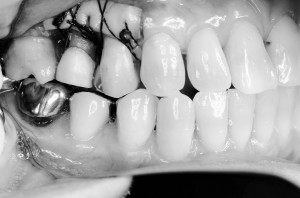

入れ歯のバネのような針金を装着し、そこにゴムをかけて引き出した行きます

1か月から2か月くらいかけて引きだすことができました

歯茎や骨も一緒に矯正によりついてくるため、調整する処置を行います。その際に歯茎が非常に薄く痩せやすい歯茎を厚みのあるボリュームのある歯茎に改善しました。これは遊離歯肉移植術という方法で、口蓋から厚い歯茎を移植し、歯ブラシがしやすく丈夫な歯茎に改善することができます。

その後歯茎の治癒を4か月程待ち、仮歯をしっかり調節していき最終的な被せ物に移行しました。